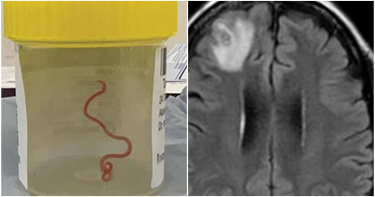

印度一名男子眼睛不適,為了避免影響視力,該名男子立刻前往醫院尋求醫生處理,結果竟從眼睛裡拉出一條寄生蟲,操作過程的影片也在網路上曝光,並且發現這種寄生蟲是藉由蚊子叮咬傳播。根據《鏡報》報導,印度一名60歲男子因眼睛感到不適,就前往當地醫院就診,結果發現眼睛裡竟藏了一條約15公分的寄生蟲,醫生立即為男子取出寄生蟲,避免影響視力。影片中,醫生拿夾子小心取出後,放到容器中寄生蟲還不斷在蠕動。這隻寄生蟲是一種叫做「班氏絲蟲」的寄生蟲,它藉由蚊子叮咬傳染;據報導,世界上第一個取出活寄生蟲時,是從澳洲一名婦人的大腦中取出的,當時這位婦人是經歷了數週的不適症狀(腹痛、腹瀉、乾咳、發燒、盜汗)後,一直到2021年1月才就醫。儘管過了1年,這位婦人情況並沒有改善,她變得健忘又罹患重度憂鬱症,因而轉院至坎培拉醫院(Canberra Hospital)。她進行磁振造影掃描後,精神科醫師認為她的大腦異常,結果手術發現在她大腦竟住著一條「8公分」的寄生蟲。這條寄生蟲讓在場醫生都非常困惑,他們無從得知這條蟲是怎麼進到該名婦女的大腦的。澳洲聯邦科學與工業研究組織(CSIRO)的專家表示,這是一種常見於蟒蛇上的羅伯氏蛇蛔蟲(Ophidascaris robertsi)。據瞭解,原來該名婦女居住在地毯蟒(carpet python)出沒的湖泊附近,雖然沒有直接接觸,但也有可能經由採集食用草本植物等原因,間接觸碰到蟒蛇糞便,而糞便中可能有寄生蟲的卵,才導致感染。

婦人大腦藏8公分活寄生蟲…醫開刀傻眼 竟只出現蟒蛇中

澳洲一名64歲女子因身體痛苦不堪,症狀持續數週,她到醫院進行腦部掃描,意外在大腦內發現一條約8公分的活寄生蟲,醫生開刀取出直接傻眼,向其他人求救。專家表示,該種寄生蟲通常只會出現在蟒蛇體內。據《鏡報》報導,患者經歷了數週的腹痛、腹瀉、乾咳、發燒等痛苦症狀,她在2021年1月下旬就醫。之後,她變得健忘又憂鬱,之後被轉到堪培拉醫院,進行了腦部斷層掃描,結果顯示有異狀,外科團隊要對她動手術。神經外科醫生班迪(Hari Priya Bandi)負責主刀,而當她從患者頭部拉出一條8公分的活寄生蟲時,她感到很傻眼,因為她不知道那是什麼,也不知蟲是怎麼到那,她因此向其他醫生求救。傳染病醫生塞納納亞克(Sanja Senanayake)表示,神經外科醫生不會認為他們發現寄生蟲,他們經常處理大腦感染,這是職涯中第一次新發現。據了解,院方召集了專家小組,來研究寄生蟲。專家一看就明白,這是羅伯氏蛇蛔蟲(Ophidascaris robertsi),通常只會出現在蟒蛇中,這讓女患者成為世界首例被羅伯氏蛇蛔蟲感染的案例。《衛報》報導,女子住在一個湖附近,那裡有許多地毯蟒棲息。塞納納亞克說,據說患者沒跟蛇有任何接觸,但她經常採草藥進行烹飪,目前推論可能是蟒蛇在排泄過程中,將寄生蟲中排到草叢中,當患者接觸或吃掉草時,就被感染了。所幸患者腦袋的寄生蟲取出後,醫生也確保沒有任何幼蟲侵入她身體的其他部位。塞納納亞克說,病患很勇敢,醫護向她致敬。